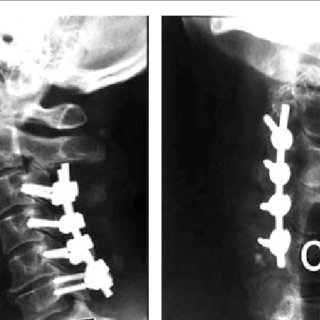

- Titanium screws and plate is attached to the two vertebrae around the area where the disk was removed.

- Titanium Lateral mass screws are inserted and joined with rods.